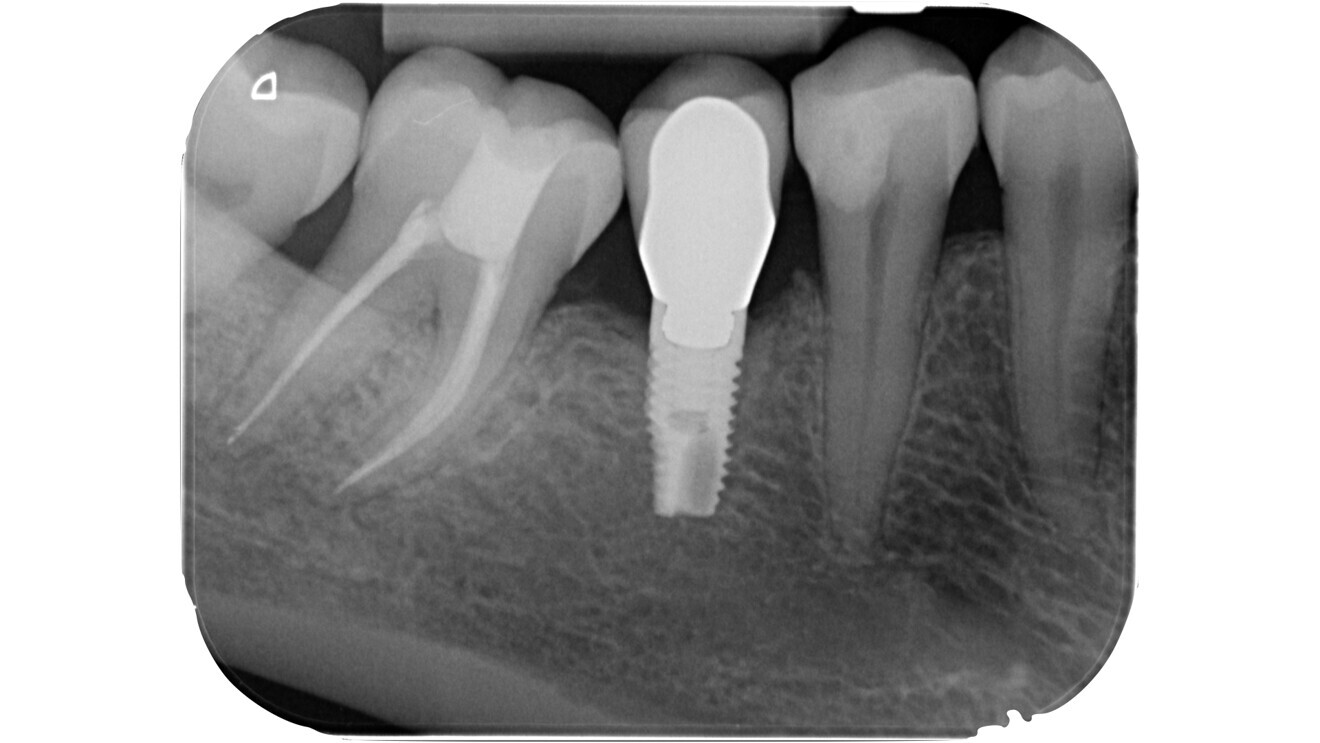

Fig. 15: Pre-op radiograph of a mandibular molar affected by irreversible pulpitis.

Fig. 16: Intermediate phase of treatment, after pre-endodontic reconstruction, access cavity preparation and preliminary canal shaping. Note the presence of a pulp stone on the floor of the chamber with a translucent appearance.